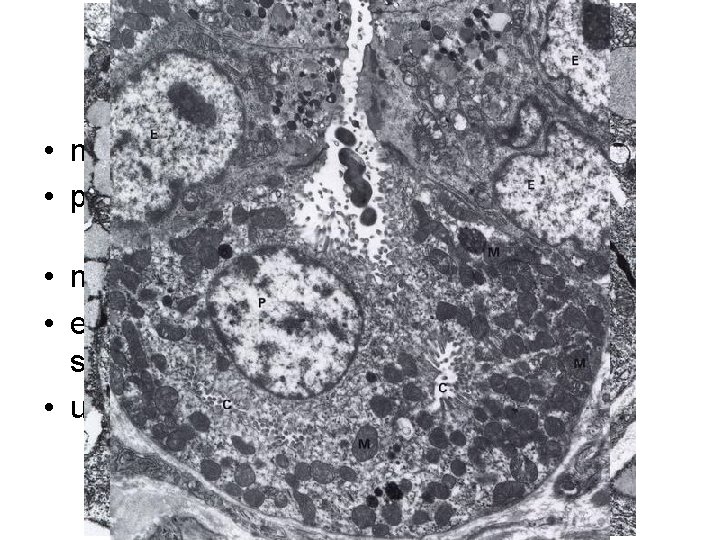

Gastric cells • main cells - pepsinogen, lipase • parietal cells - HCl, intrinsic factor • abundant intracellular channels • mucinous cells – mucus • enteroendocrine cells (DNES) - gastrin, somatostatin • undiferentiated cells - mitotically active

Synthesis of HCl • in parietal cells • Cl- - from plasma • H+ - from H 2 CO 3 – by carboanhydrase from CO 2 and H 2 O